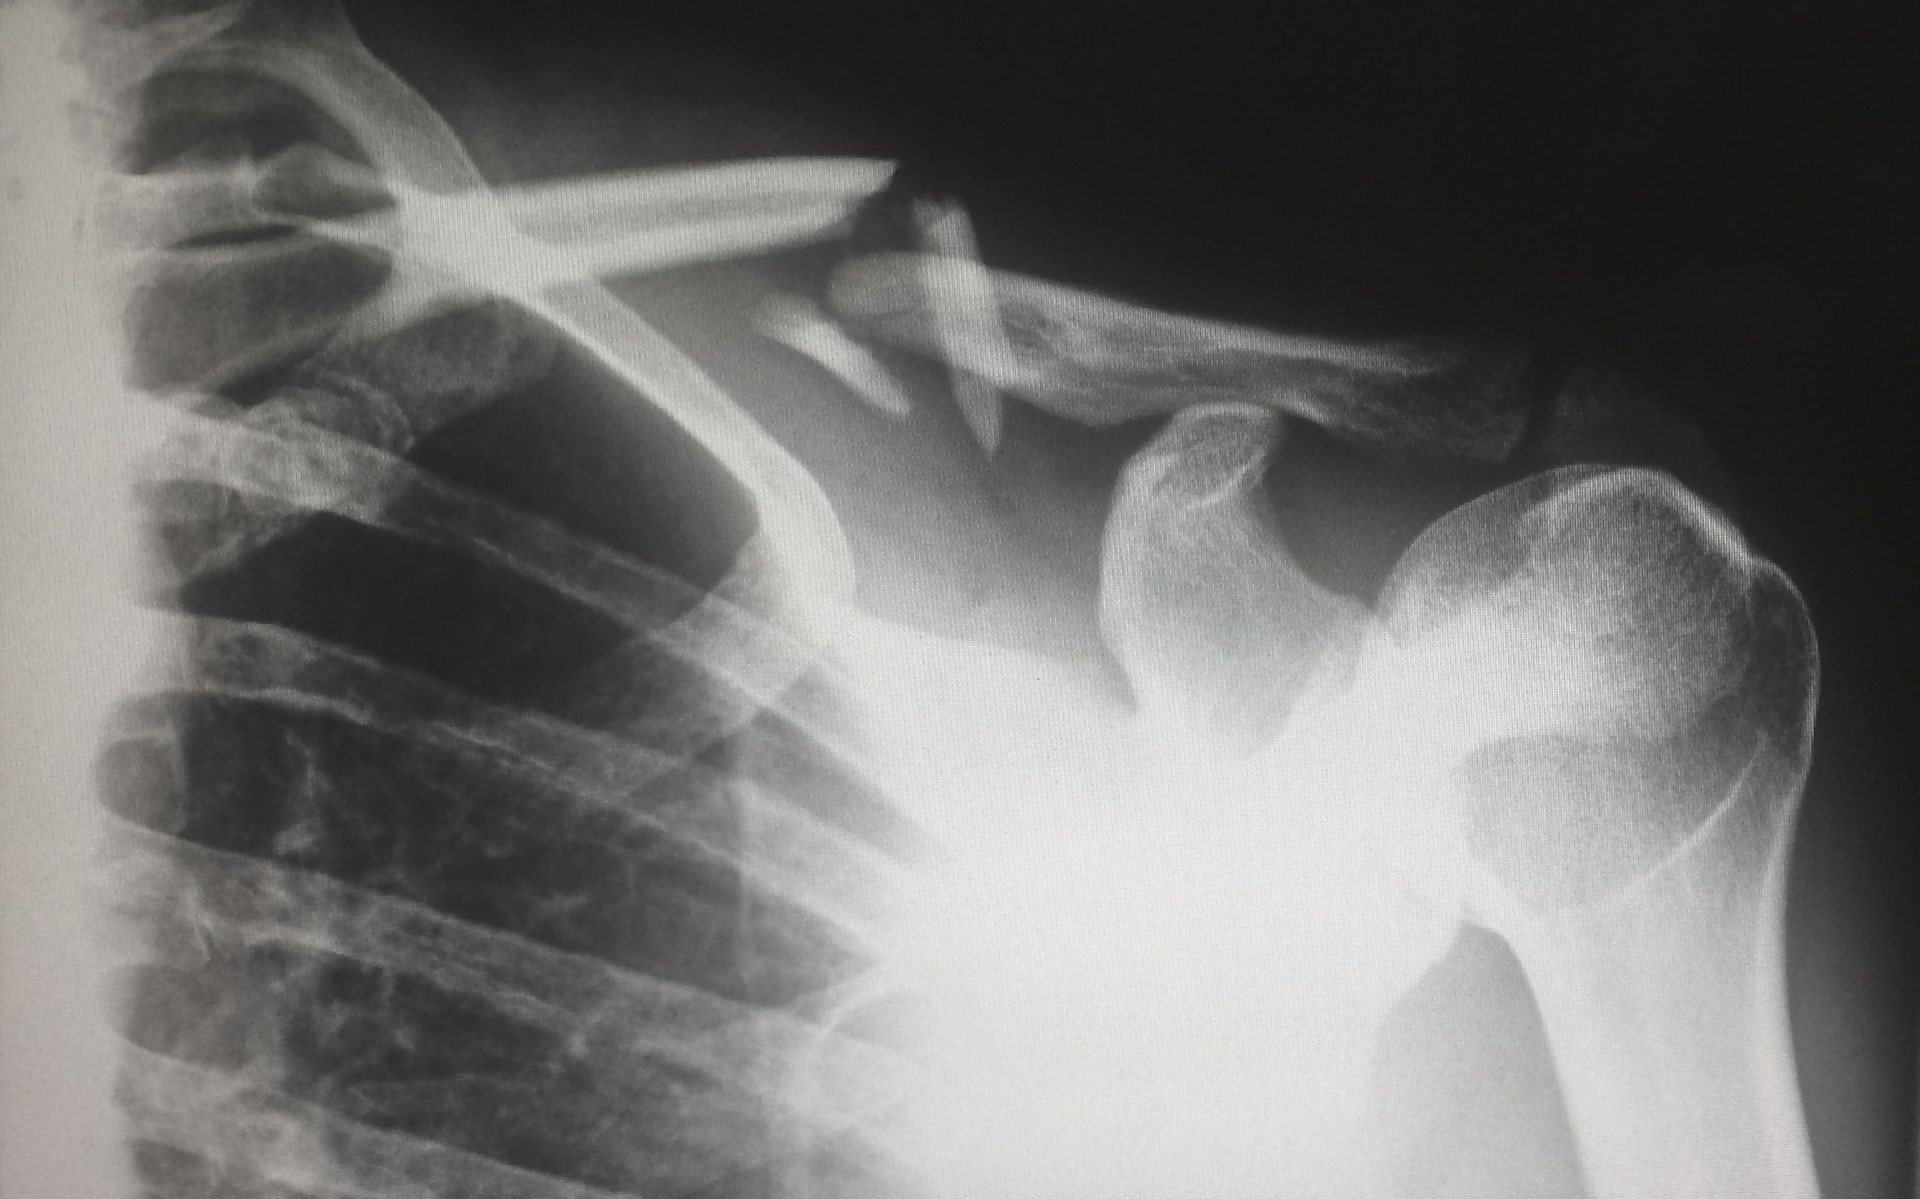

There are many reasons surgeons may need to transition to a different surgical treatment option during shoulder arthroplasty procedures, including humeral bone quality and severity of glenoid bone loss, or the extent of rotator cuff deficiency. The system allows surgeons to treat a broad range of cases by providing an intelligently-designed implant offering that is both streamlined and comprehensive, and also features unique interoperative flexibility, addressing a critical unmet clinical need. The common instrumentation of the INHANCE Shoulder System also facilitates greater OR efficiency.